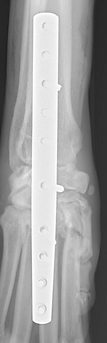

Treatment for carpal hyperextension injury is surgical, involving arthrodesis (joint fusion).

Depending on the extent of injury, this may involve:

After surgery, splinting or bandaging is required to protect the limb during healing. With proper surgical technique

and postoperative care, most dogs and cats regain strong, comfortable limb function.